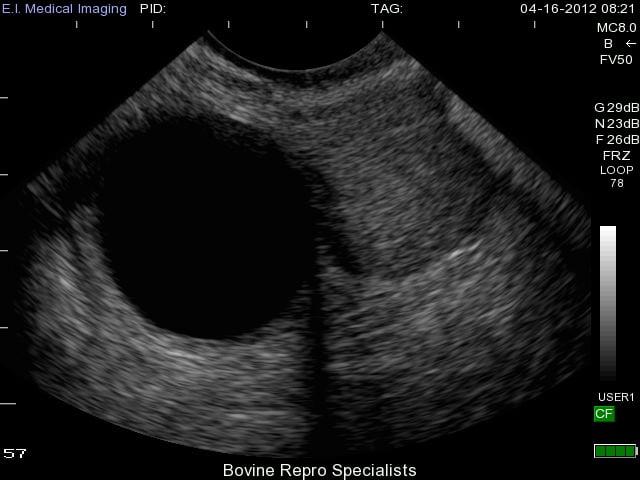

With luteal cysts originating from follicular cysts, the same mechanisms for follicular cysts development described above exist for luteal cysts. The major distinguishing factor between the two is that luteal cysts partially luteinize. Luteal cysts can also have different appearances on the ultrasound depending on the rate of luteinization. This is apparent in the next two images below depicting more examples of luteal cysts. You can see in this first image that luteinization has occurred along the bottom rim of the cyst and again the cobwebs of fibrous tissue are attempting to luteinize the rest of the cyst, but the upper portion of the lumen is still fluid-filled.

This second image is a luteal cyst (on the right side of ovary) in its early stages where the thin outer walls of the cyst still resemble that of a follicular cyst, but the cobwebs are apparent throughout the lumen as the cyst attempts to luteinize. You can see a second cyst on the left side of the ovary as well.